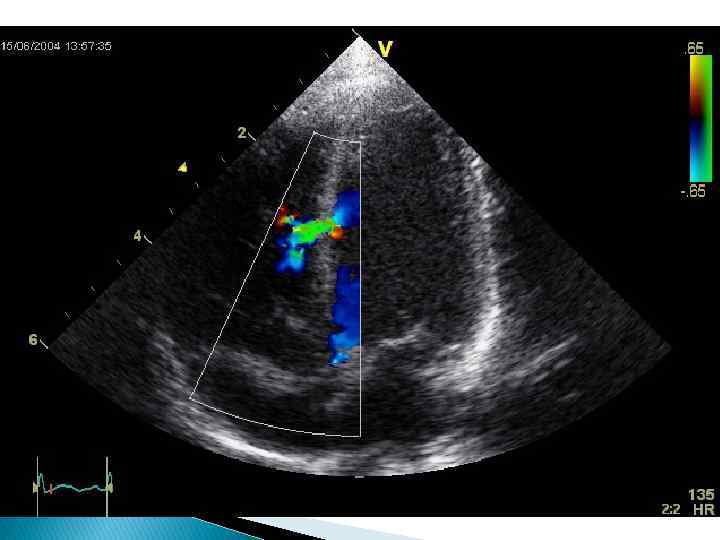

Средние и Большие Дефекты Инструментальная диагностика: Эхокардиографическое исследование дает исчерпывающую информацию о наличии дефектов в перегородке. Ребенок – 3 года. Диагноз врожденный порок сердца, дефект межжелудочковои перегородки В средней трети мышечной части перегородки лоцируется дефект (VSD) диаметром 6 мм Умеренное увеличение левого желудочка (LV) с незначительном гипертрофиеи его стенок Ребенок – 2 года. Диагноз врожденный порок сердца, дефект межжелудочковои перегородки Модифицированная 4 камерная позиция Апикальным доступ Лоцируется высокии мем-бранозныи ДМЖП (VSD) диаметром 12 мм с фиброзными краями